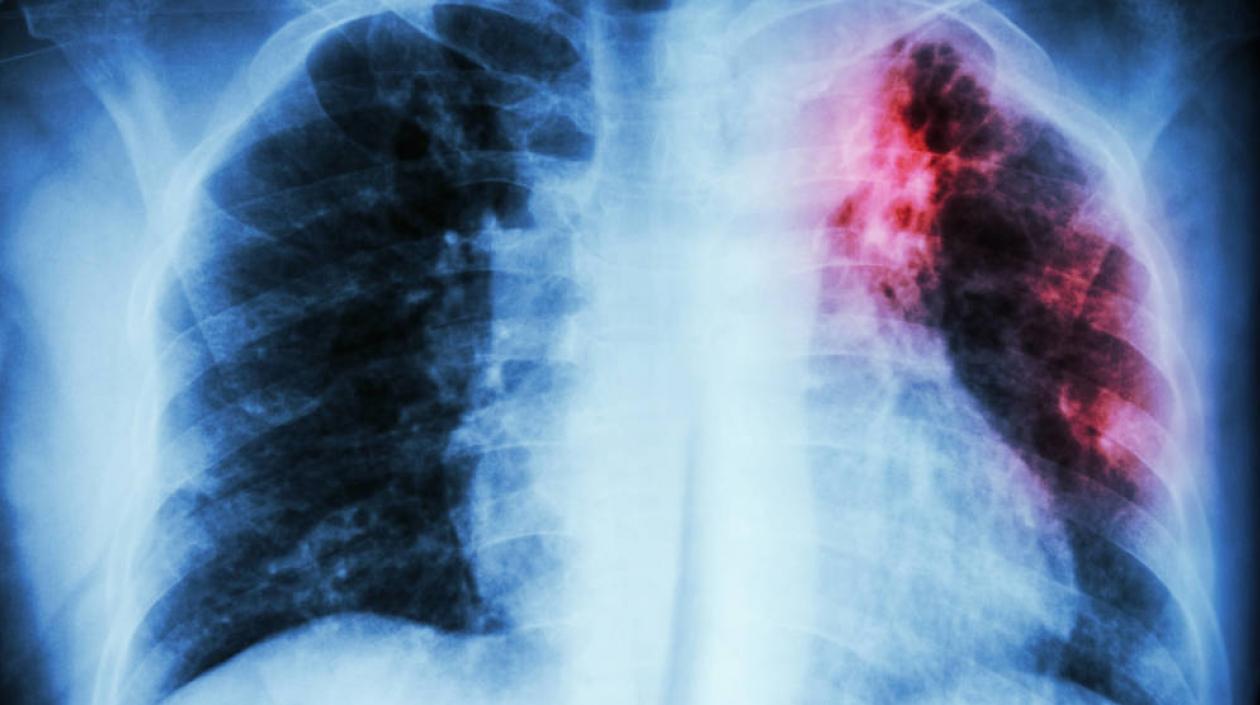

La fibrosis pulmonar hace que el tejido del pulmón desarrolle cicatrices.

La fibrosis pulmonar hace que el tejido del pulmón desarrolle cicatrices que causan la pérdida progresiva de la capacidad respiratoria.